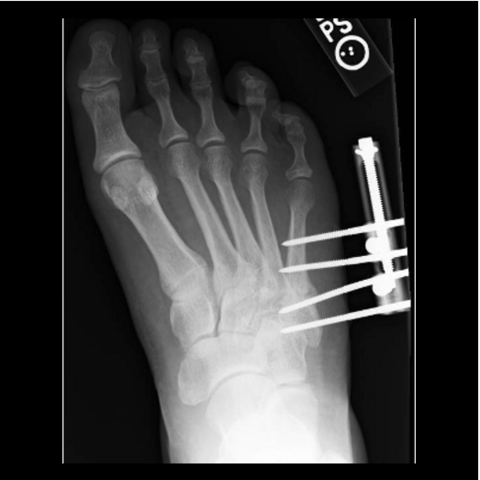

Figure 5a

Figure 5a. The 24-year-old required hardware removal and application of external fixation for gradual compression. Most cases heal within 6 weeks with gradual compression weekly.

-

Figure 5b